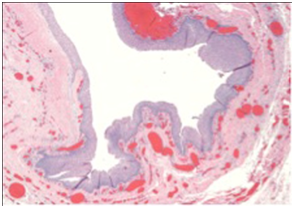

Two theories describe the potential origin of these cysts: congenital versus acquired. Congenital cysts result from entrapment of epithelium secondary to failure of surface ectoderm regression and acquired cysts are secondary to infection or trauma.1,2,5 During the third to fourth weeks of intrauterine life, the first and second brachial arches fuse. A cyst may arise if the tissue becomes confined during the fusion. Acquired cysts are believed to arise from epithelial cell embedded in deeper tissue5,6 (Figure 2).

Figure 2(a & b) Pathologic confirmation of dermoid cyst. Gross examination of specimen revealed a pink-tan cyst measuring 2.2 x 2 x 1.5 centimeters. Histologic examination showed squamous epithelium with scattered mucous glands consistent with dermoid cyst.